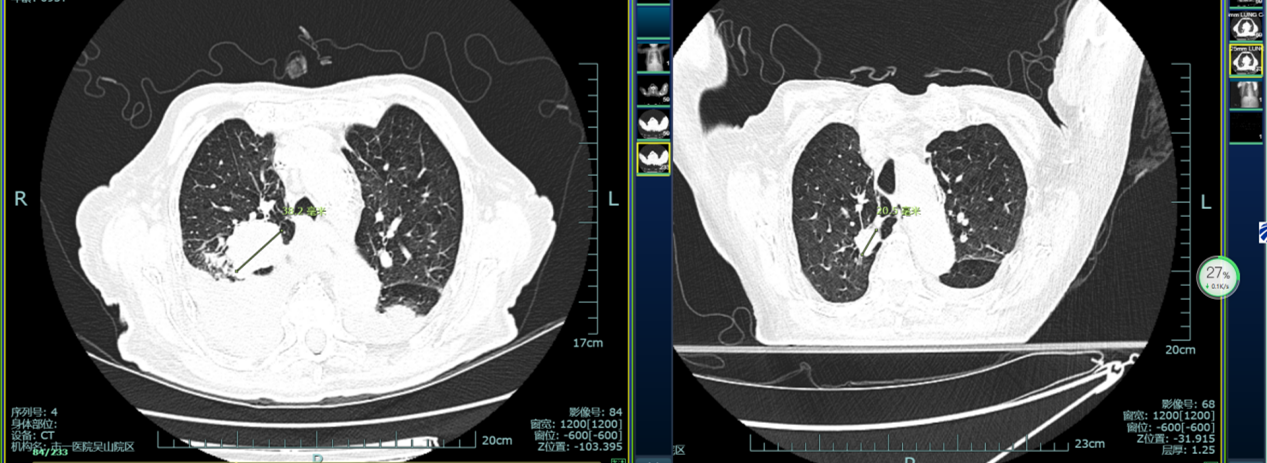

治疗前后对比图

经过一个月的精心治疗和护理,复查结果令人欣喜:右肺原发灶较前缩小,肺内多枚小结节及类结节较前缩小、减少,双侧胸腔少量积液,较前减少。更难得的是,李奶奶全程无不适,连血象都保持正常。这个结果让医疗团队和家属都倍感欣慰。